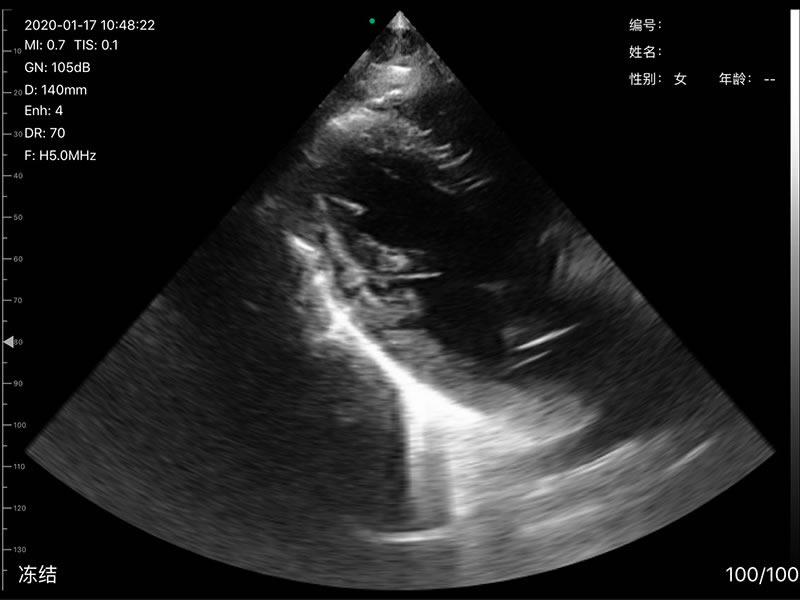

• 探头频率:相控阵2.2/3.6MHz,线阵7.5/10 MHz

• 扫描声头:同时具备微凸、线阵两个声头,并可通过按键快速切换

• 扫描深度:相控阵20-240mm,线阵 20-100mm,可调

• 扫描角度和宽度:相控阵80mm,线阵25mm

• 显示模式:B、B/M、Color、PW、PDI